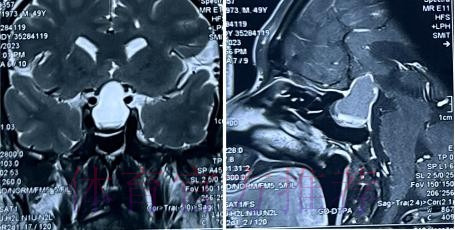

核磁结果传来 塞巴略斯躲过最坏结局的背后

当一名核心中场在比赛中突然倒地捂腿时,球迷脑海里往往会瞬间闪过无数画面 从长时间缺阵 到赛季报销 再到球队体系被迫重建 尤其是像塞巴略斯这样技术细腻 跑动积极的球员 任何一次伤病消息都足以牵动无数人的心 正因如此 当外界最初传出他伤情不明 甚至可能较为严重的风声时 不少人已经开始预设他长期缺阵的最差方案 然而经核磁共振检查确认 塞巴略斯伤情没有预期严重 这一诊断结果 不仅让俱乐部和球迷长舒一口气 也提供了一个审视现代足球伤病管理的绝佳切入口

从恐慌到冷静 影像学检查给出的真实答案

在高速对抗的现代足球里 现场肉眼和赛后情绪往往会放大对伤情的判断 一名球员倒地呻吟或无法坚持比赛 很容易被解读为韧带断裂 或肌肉严重撕裂 但真正决定恢复周期的关键因素 通常要到核磁共振检查之后才会明朗 因为核磁能在较早阶段清晰显示软组织 肌肉 韧带以及骨结构的微小损伤情况 对伤情做出更接近真相的分级判断 塞巴略斯此次就是典型案例 初步观感可能让人联想到更严重的伤病 但核磁提示伤情相对可控 没有出现完全断裂或大面积撕裂 也就意味着他不需要漫长的康复旅程 只要遵循医学建议 科学负荷管理 就有机会用较短的时间重新回到训练场和比赛中